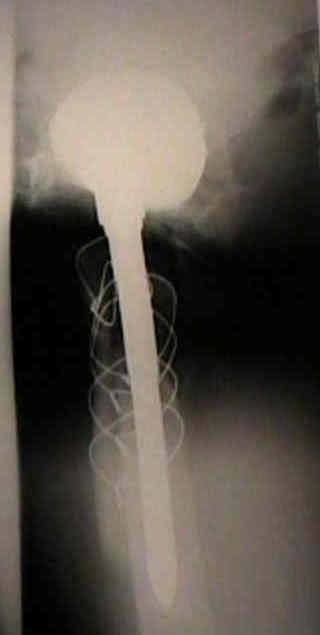

Loosening of Press Fit Acetabular Components

radiographic signs of ingrowth fixation

radiographic signs of loosening

Loosening of Cemented Acetablar Components